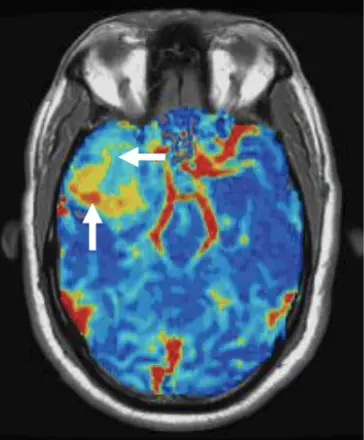

IB Neuro is an exclusive MRI perfusion platform that generates quantitative relative cerebral blood volume (rCBV) maps. The quantitative output has undergone independent validation with tissue samples and has been shown to far exceed the accuracy and repeatability over other perfusion methods. With over 30 years of pioneering development, this cutting-edge technology excels in differentiating tumor types, predicting tumor grades, and distinguishing post-treatment effects from tumor recurrence. It is the only platform proven reliable using 50% less gadolinium-based contrast agent for both 1.5T and 3T. Additionally, IB Neuro processes CT perfusion datasets, making it an indispensable tool in advanced neuroimaging.

IB Neuro automatically generates standardized sRCBV maps that quantify tumor vascularity with clarity and consistency—streamlining decision-making across neuro-oncology care.